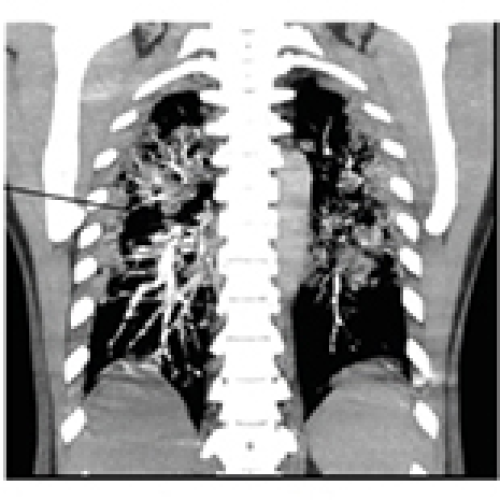

14 Nov 2021 : Clinical Research

Clinical Features and Temporal Lung Radiographic Changes in 25 Patients Recovering from COVID-19 Pneumonia: A Retrospective Case-Control Study

Chao Hu, Jian Ping Zeng, Ke Peng, Hong Xia, Huan Ming Zhang, Zhi Zhong, Ming Yan Jiang

DOI: 10.12659/MSM.933381

Med Sci Monit 2021; 27:e933381

3,640 973 0

3640 973 0